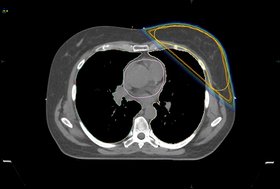

• Screenshot Deep-Inspiration-Breath-Hold-Technik (DIBH): Nach tiefer Einatmung (rechts) sieht man, wie sich die Lunge im Vergleich zur Atemmittellage (links) ausdehnt und sich das Herz gleichzeitig weit von der linken Brustwand entfernt. So kann eine herz- und lungenschonende Bestrahlung der linken Brust problemlos durchgeführt werden.

(Quelle: Klinikum Bremen-Mitte/Fachärztezentrum Hanse)